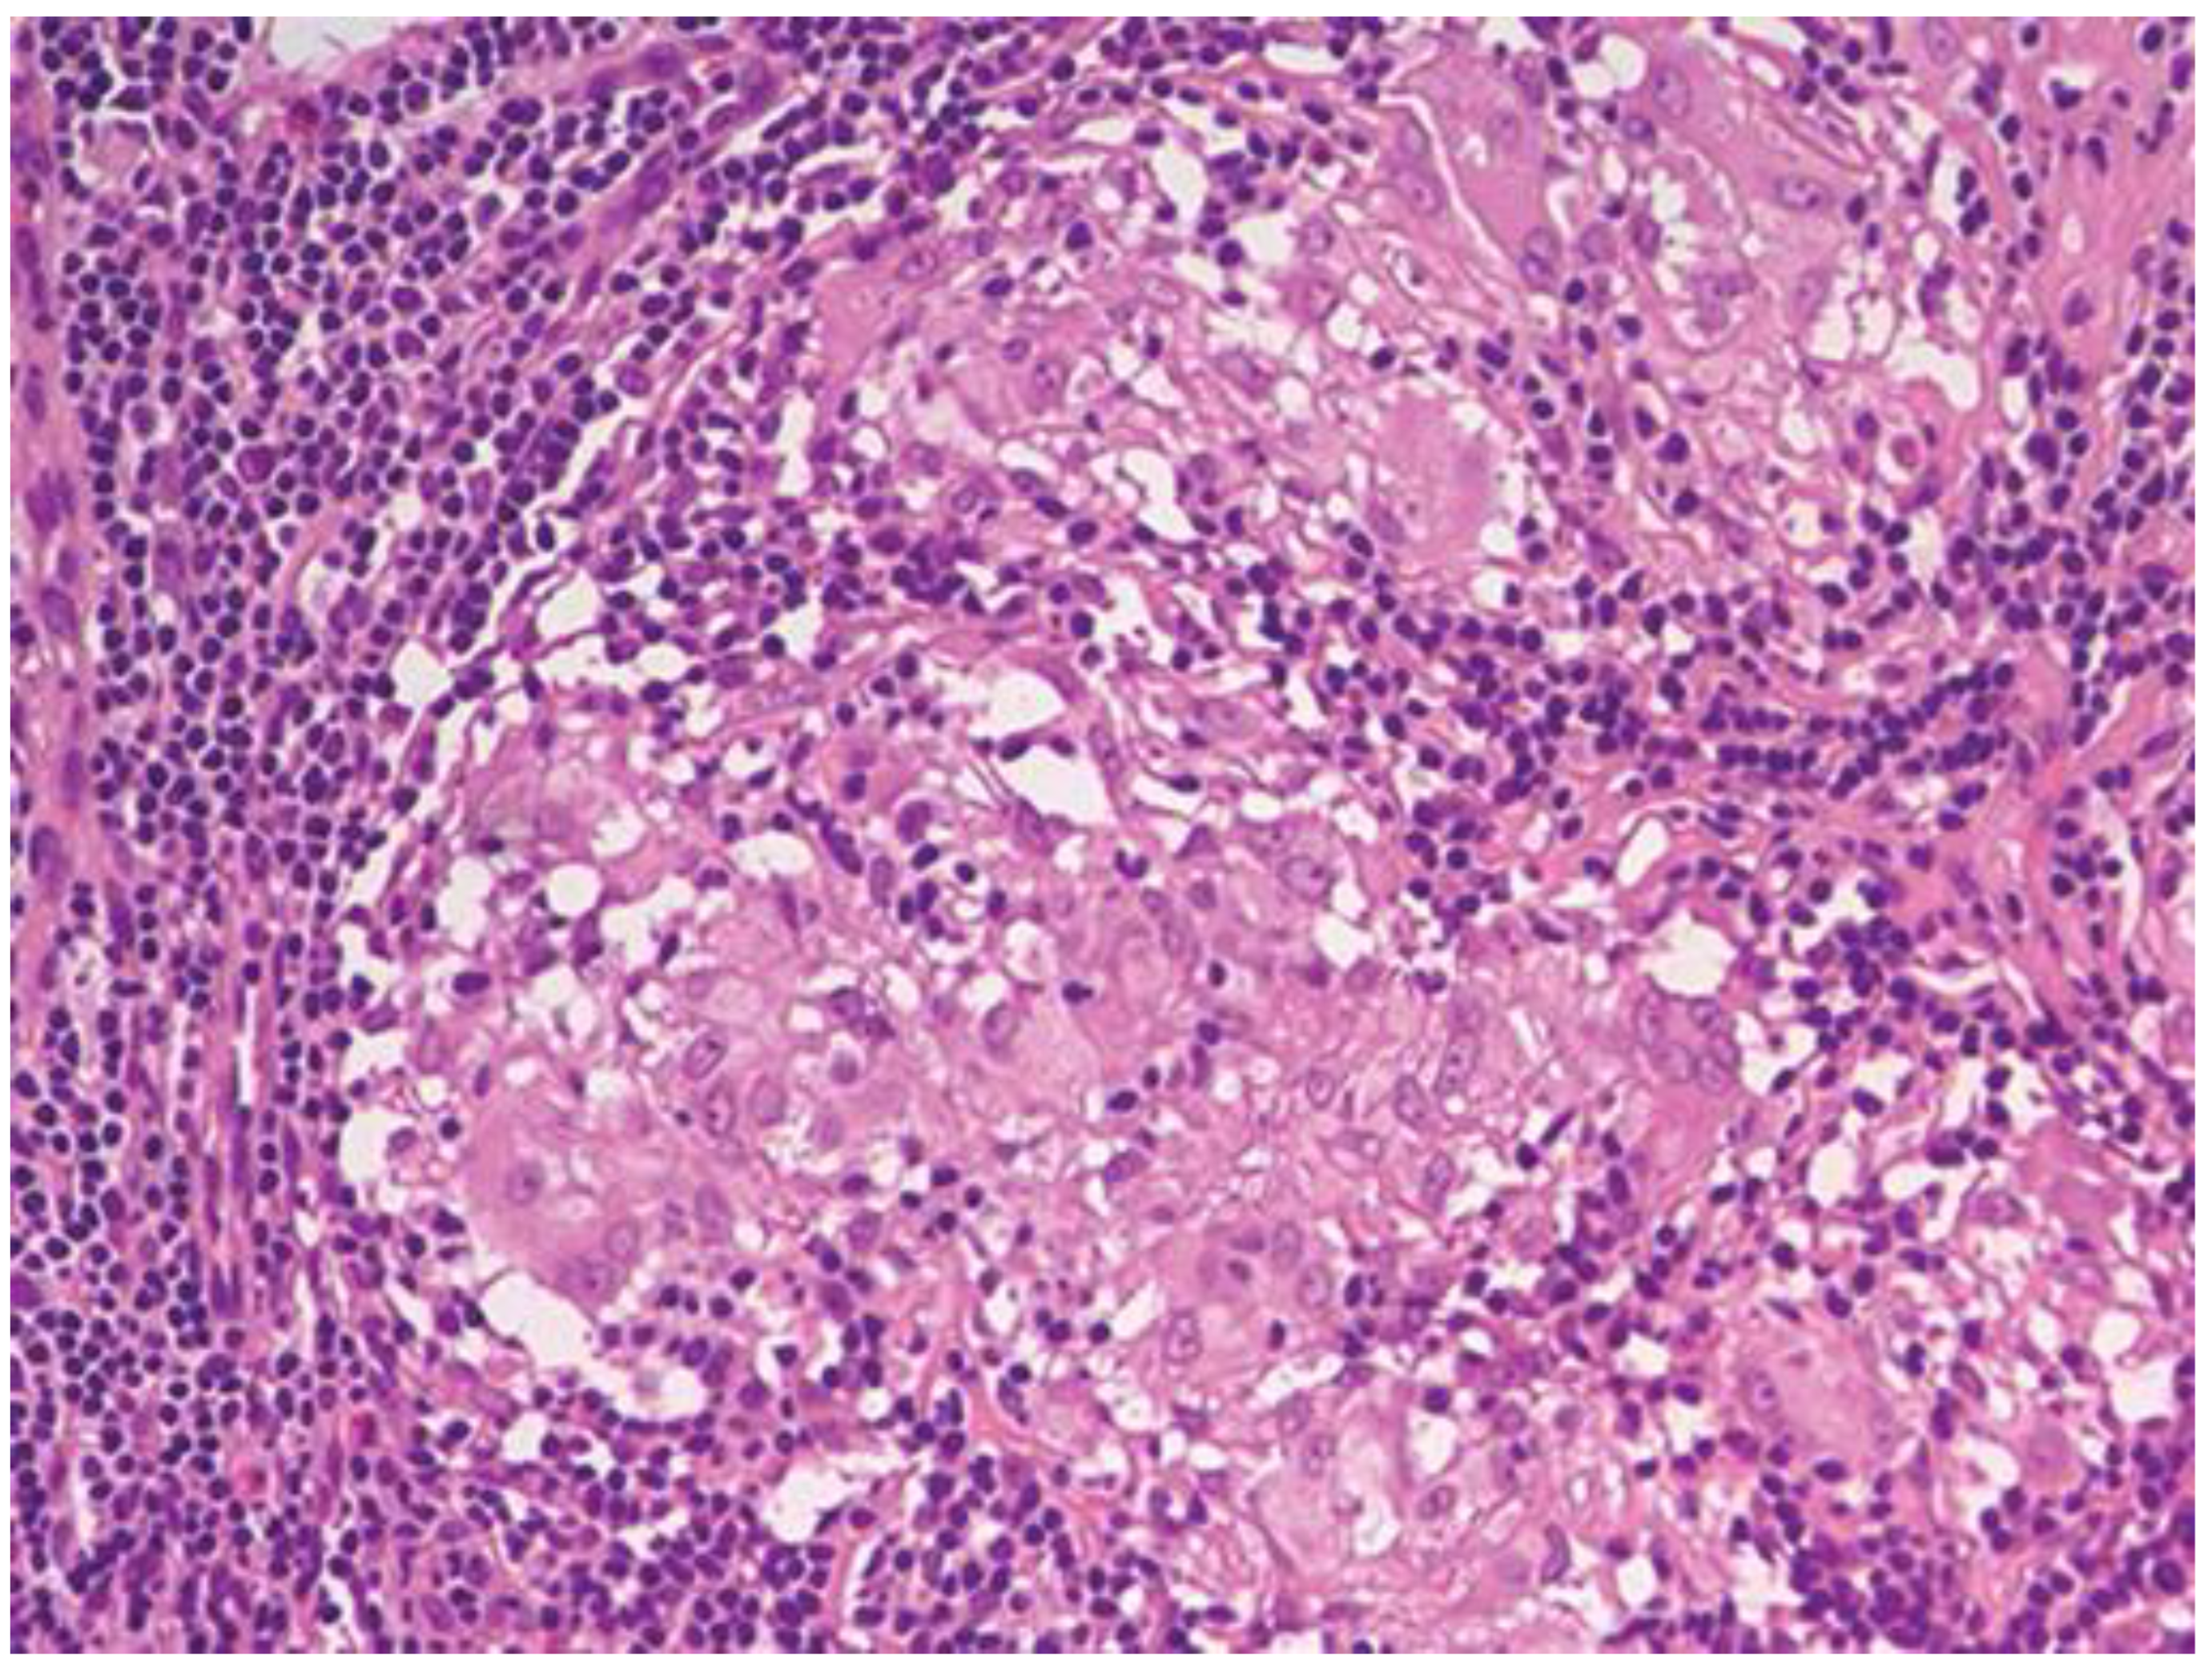

Фотографии опухоли медуллярной аденокарциномы